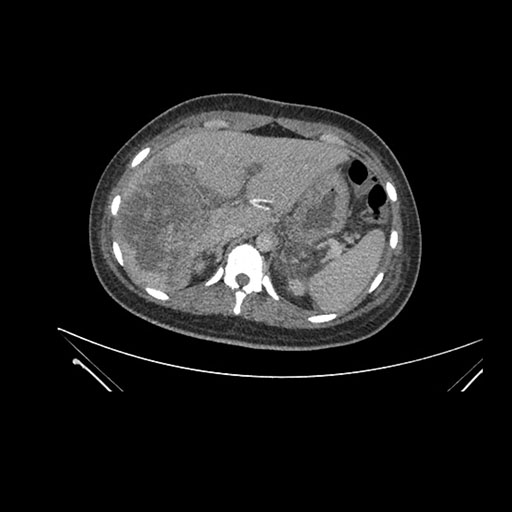

Imaging Analysis

Look through the patient's CT scan to identify any areas of concern for the necessary procedure.

Coronal Arterial

Based on initial findings, which issue(s) would you be most concerned about?